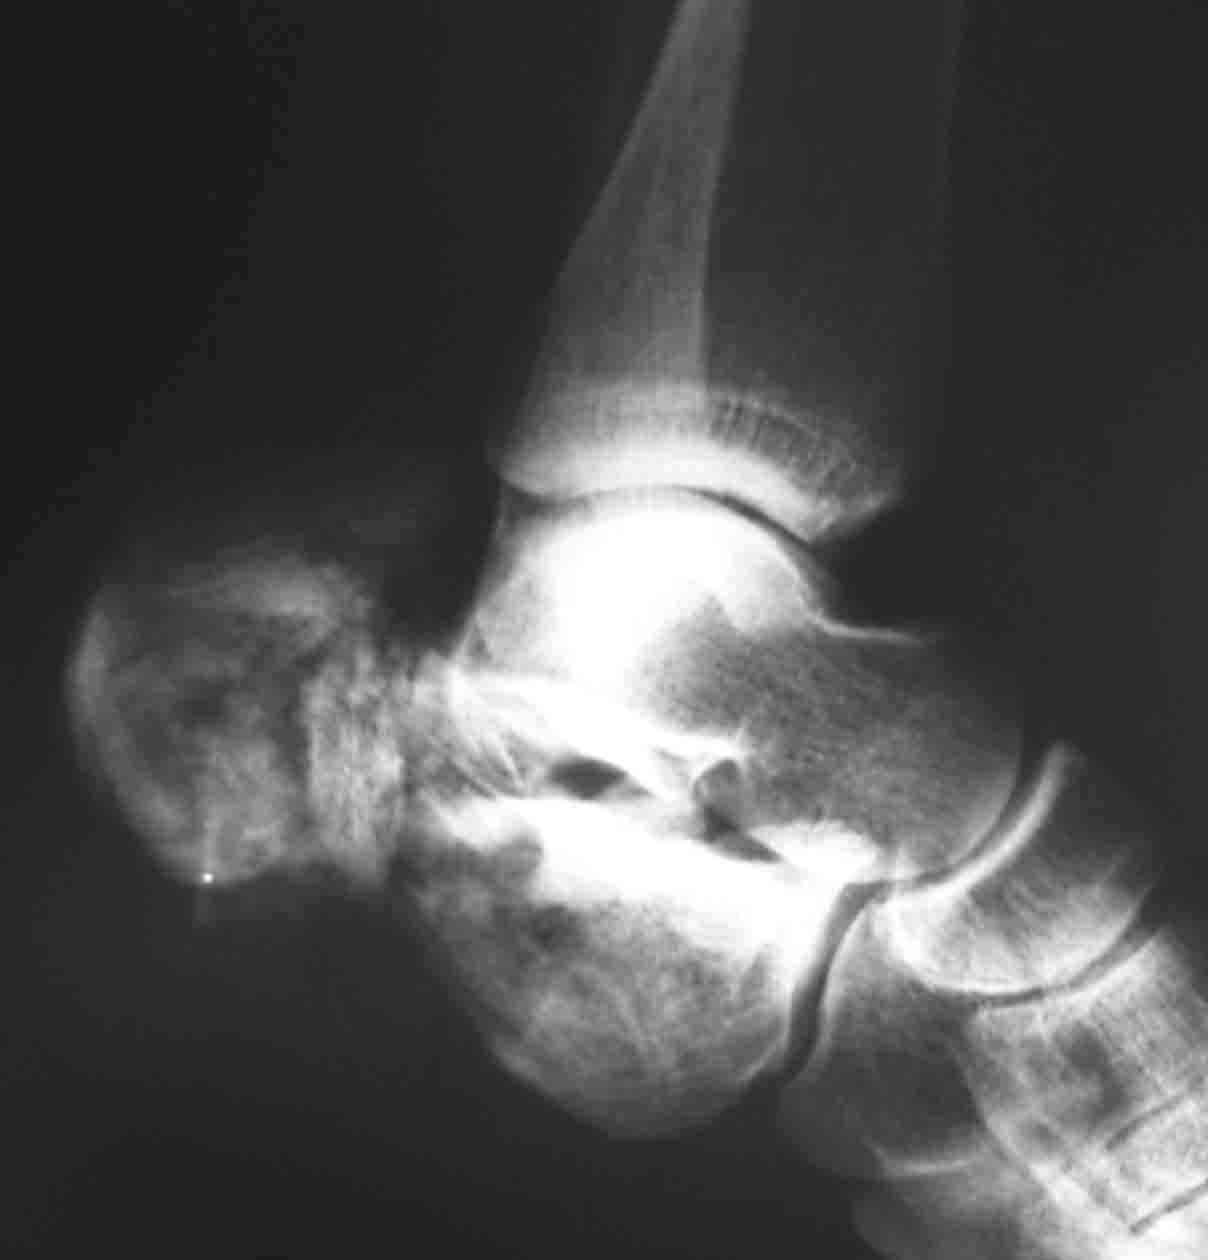

Пациентка 26 лет поступила в больницу 9 дней назад после кататравмы (падение с 4-го этажа)Тяжелая сочетанная травма: Ушиб головного мозга средней тяжести.З/полифокальный перелом таза (оскольчатый чрезвертлужный справа, латеральной массы крестца слева со смещением отломков. З/оскольчатый перелом н/3 правого бедра. З/оскольчатый перелом правой пяточной кости. Тупая травма живота - разрыв слизистой толст кишечника, кисты яичника.

мне кажется,что вначале стоит стабилизировать таз , лучше уж вариант АВФ таз-бедро . возможно стоит захватить в аппарат и дистальный перелом бедра.на таз , конечно , циркулярный аппарат с модулем на бедро . провести максимально возможную репозицию , что облегчит потом возможную внутреннюю фиксацию в любом,понравившемся вам варианте . а вот что делать с пяткой??????я бы попытался аппаратом восстановить опорную точку (бугор). существует опасность некроза мягких тканей в области бугра .

Первым этапом штифтование бедра, лучше длинная Gamma, чко пяточной кости в максимально простой комплектацией (с пяткой можно будет разобраться позже, результат все равно будет "не очень", так что, скорее всего, дело закончится артродезом), вытяжение за мыщелки бедра 12-15 кг. Вторым этапом (максимально рано, насколько это возможно) внутренний остеосинтез вертлужной впадины (планирование и выполнение доступов можно посмотреть на http://odoc.ru/art_cont.php. Похоже, что вы имеете дело с низким двухколонным переломом, для уточнения необходимы проекции Judet.